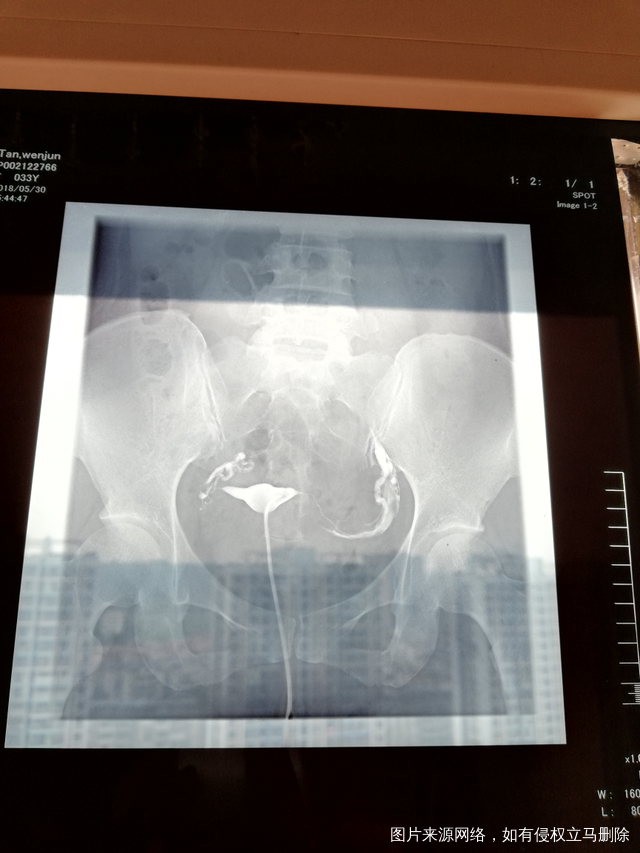

输卵管造影,双侧走行迂曲、僵硬,右侧末端弥散欠佳。